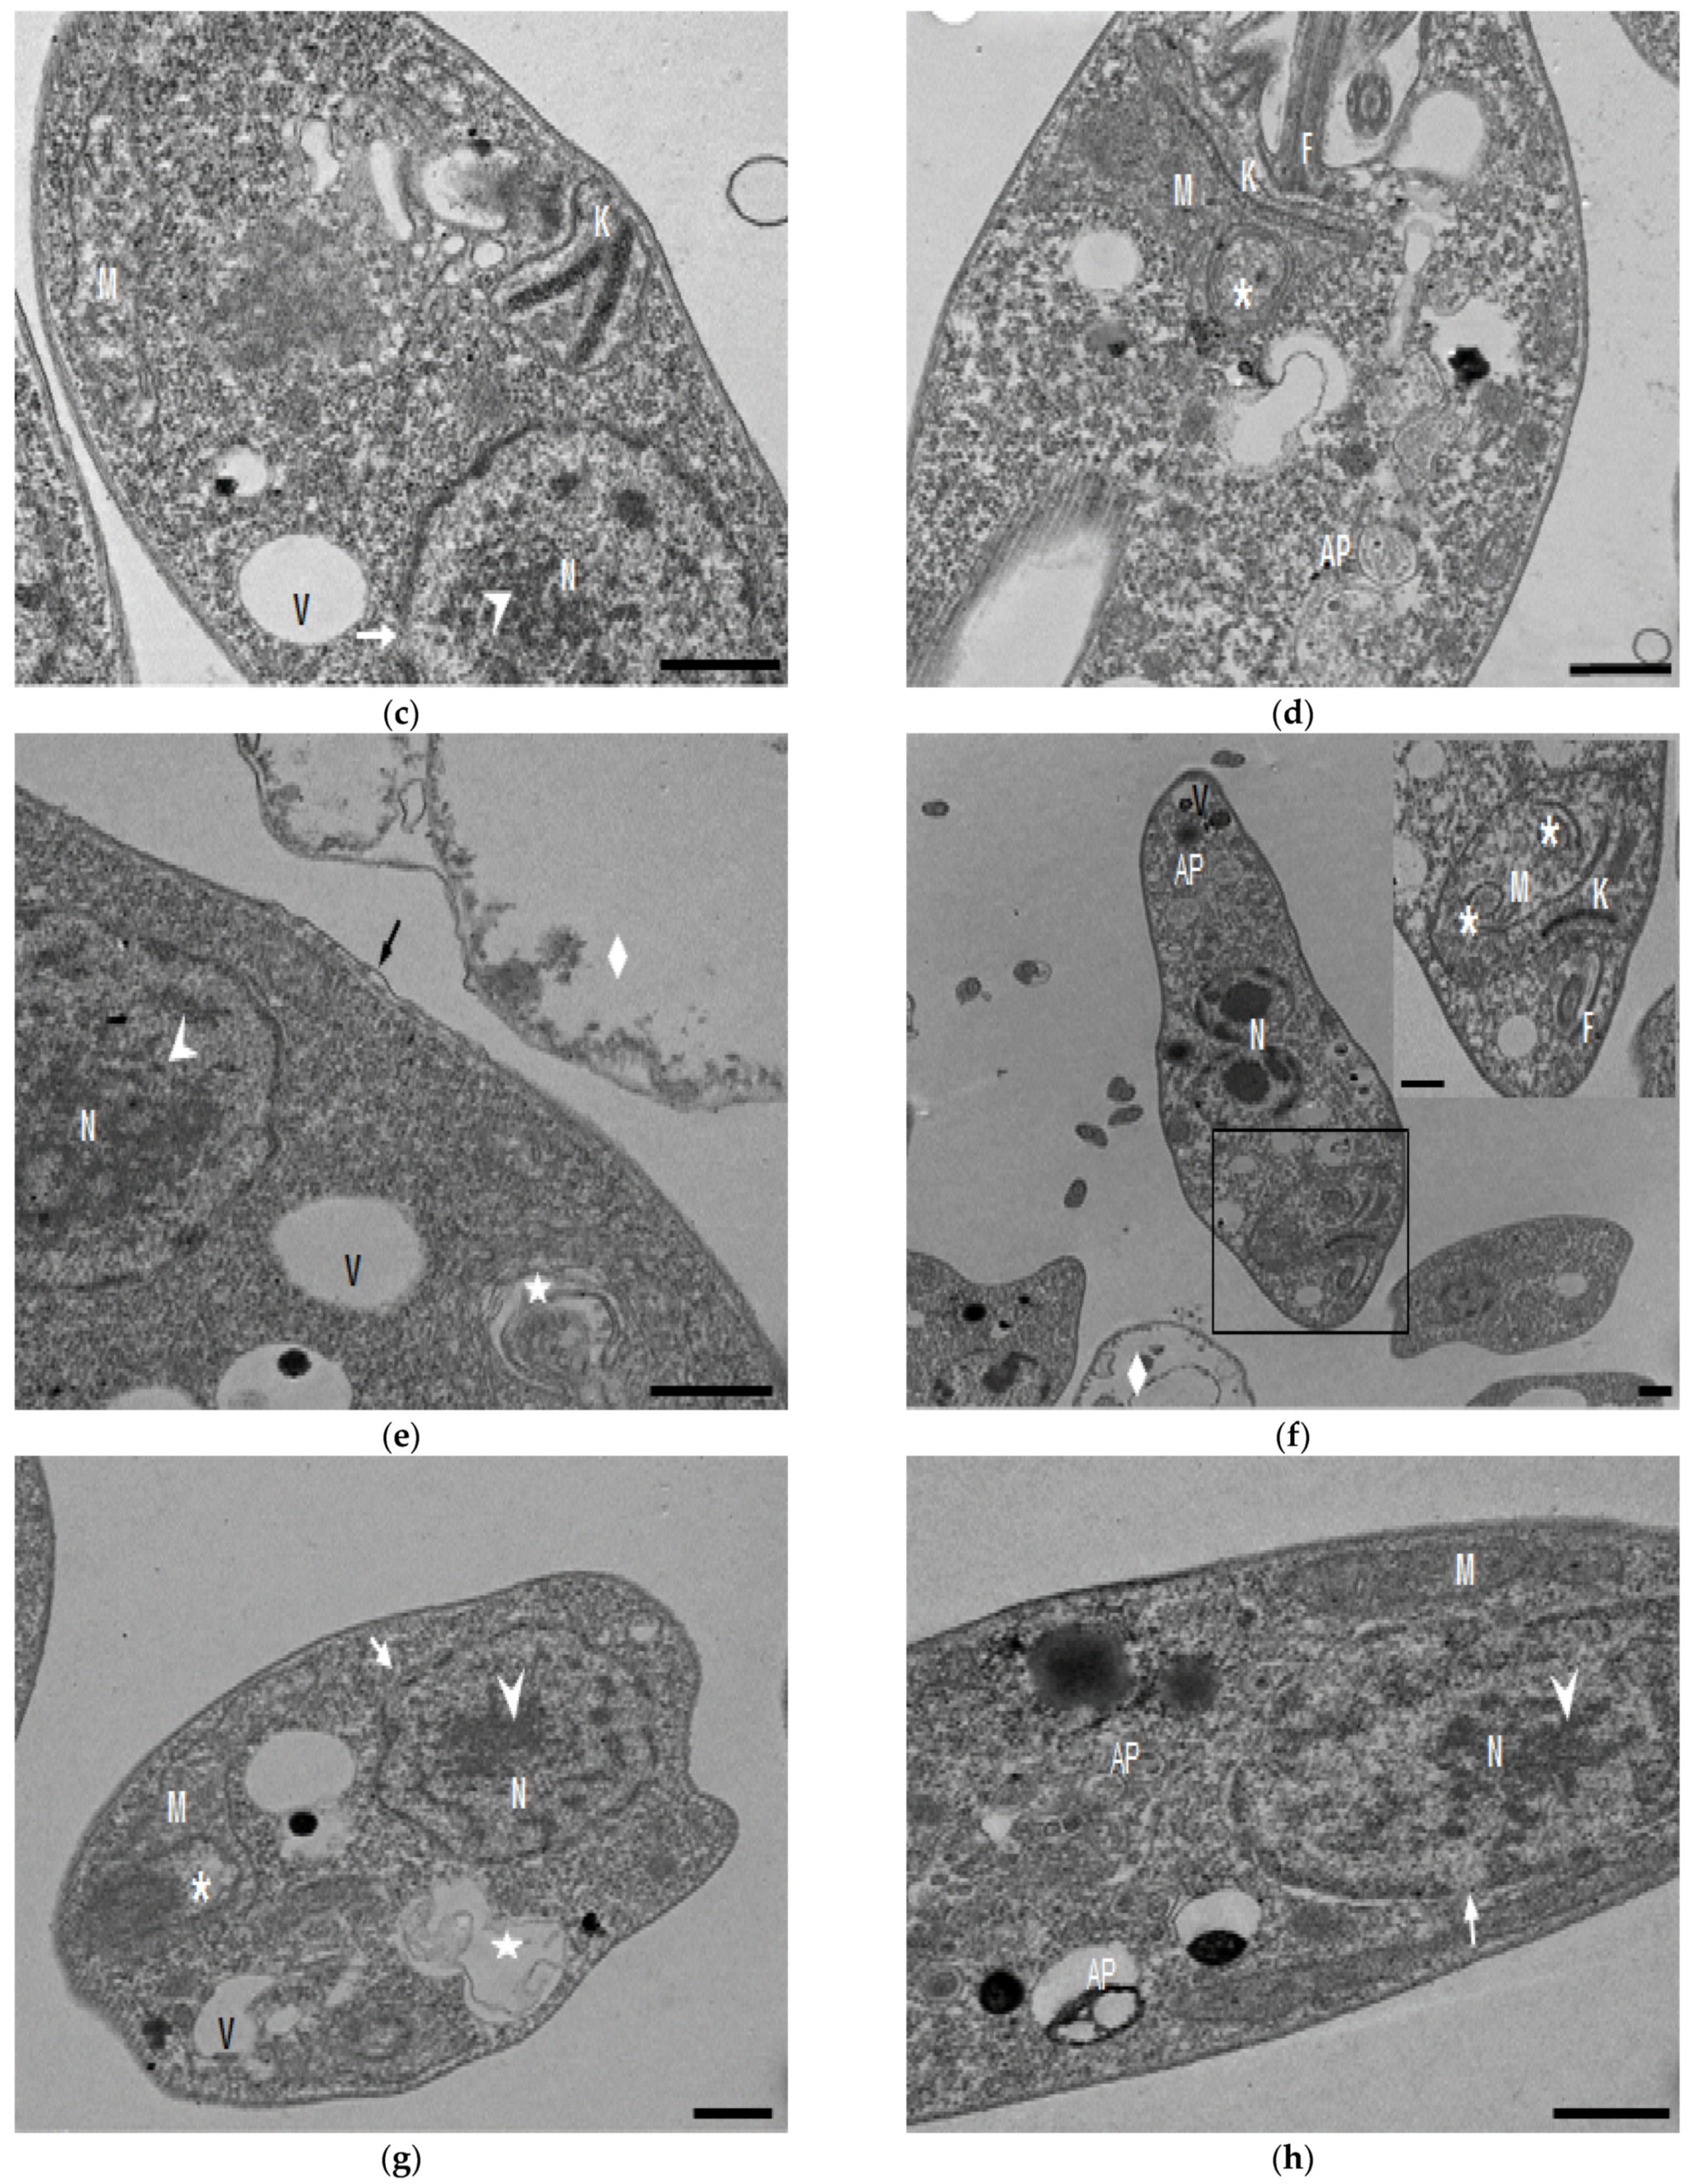

In the TEM studies (Figure 2), the control parasites were found to have plasma membranes and their characteristic structures without any damage (Figure 2a). However, the parasites treated for 6 h at 0.32 µM showed some early effects induced by compound 8 (Figure 2b–d). Some ultrastructural changes were evident such as the formation of autophagosomes and mitochondrion swelling with the presence of concentric membranal structures inside as well as an exocytic activity in the flagellar pocket, detachment of the flagellar membrane and alterations in the kinetoplast. Meanwhile, at 3.2 µM for 12 h (Figure 2e–h), the treated parasites showed even more profound changes such as the presence of increased vacuolization and autophagosomes, cytoplasmic myelin-like figures, plasma membrane detachment, rupture of the nuclear membrane and abnormal chromatin condensation. Total mitochondrion disorganization with swelling and concentrical membranes inside and, in some cases, the loss of cell integrity and cytosolic content were also observed.

Figure 2.

TEM analysis of L. mexicana promastigotes: non-treated (a) and treated with compound 8 at 0.32 µM 6 h (b–d) and 3.2 µM for 12 h (e–h). Control parasites show a normal morphology. Parasites treated with compound 8 show the presence of autophagosomes (APs) (d,f,h) and several alterations such as flagellar membrane detachment (black arrow) and exocytic activity in the flagellar pocket (black arrowhead) (b), kinetoplast structural alterations (c), mitochondrion swelling and concentric membranes inside (asterisks) (d,f,g), chromatin condensation (white arrowhead) (c,e,g,h), rupture of nuclear membrane (white arrow) (c,g,h), plasmatic membrane detachment (black arrow) (e) and cytoplasmic myelin figures (white stars) (e,g); loss of cell integrity and cytosolic content (white rhombus) (e,f); nucleus (N), mitochondrion (M), flagella (F), flagellar pocket (FP), kinetoplast (K), acidocalcisome (Ac), lipid body (LB), vacuole (V) (bar = 0.5 µm).

In the present study, with an interest in continuing the characterization of compound 8’s leishmanicidal activity, SEM studies were performed. It was demonstrated that compound 8 induced important ultrastructural changes in L. mexicana promastigotes such as membrane blebbing resembling an apoptotic-like process [20] and alterations in the flagella structure. In addition, TEM studies revealed alterations in the kinetoplast structure and profound mitochondrion damage including swelling and the presence of concentric membranes inside the organelle. We also observed cytoplasmic myelin-like figures indicative of an autophagy process, among other changes. Similar findings were described when L. amazonensis promastigotes were treated with Miltefosine [20], antifungal azoles [21] and calpains inhibitors [22]. In trypanosomastids, severe mitochondrion damage as well as an intense autophagy process and subsequent apoptosis cell death was related to a significant increase in reactive oxygen and nitrogen species (ROS and RNS) [23]. Parasites are exposed to extracellular ROS during their entire life cycle in the insect vector, as well as during the invasion of mammalian host cells [24], but ROS are also produced within the parasite through its electron transport chain or drug detoxification. In the present study, it was demonstrated that compound 8 triggers the production of ROS and parasite apoptosis, indicating that intracellular ROS production induced with compound 8 could be related to mitochondrial damage, as well as membrane blebbing and myelin-like figures observed in the SEM and TEM studies. Parasite apoptosis induced with compound 8 was demonstrated in the flow cytometry studies.